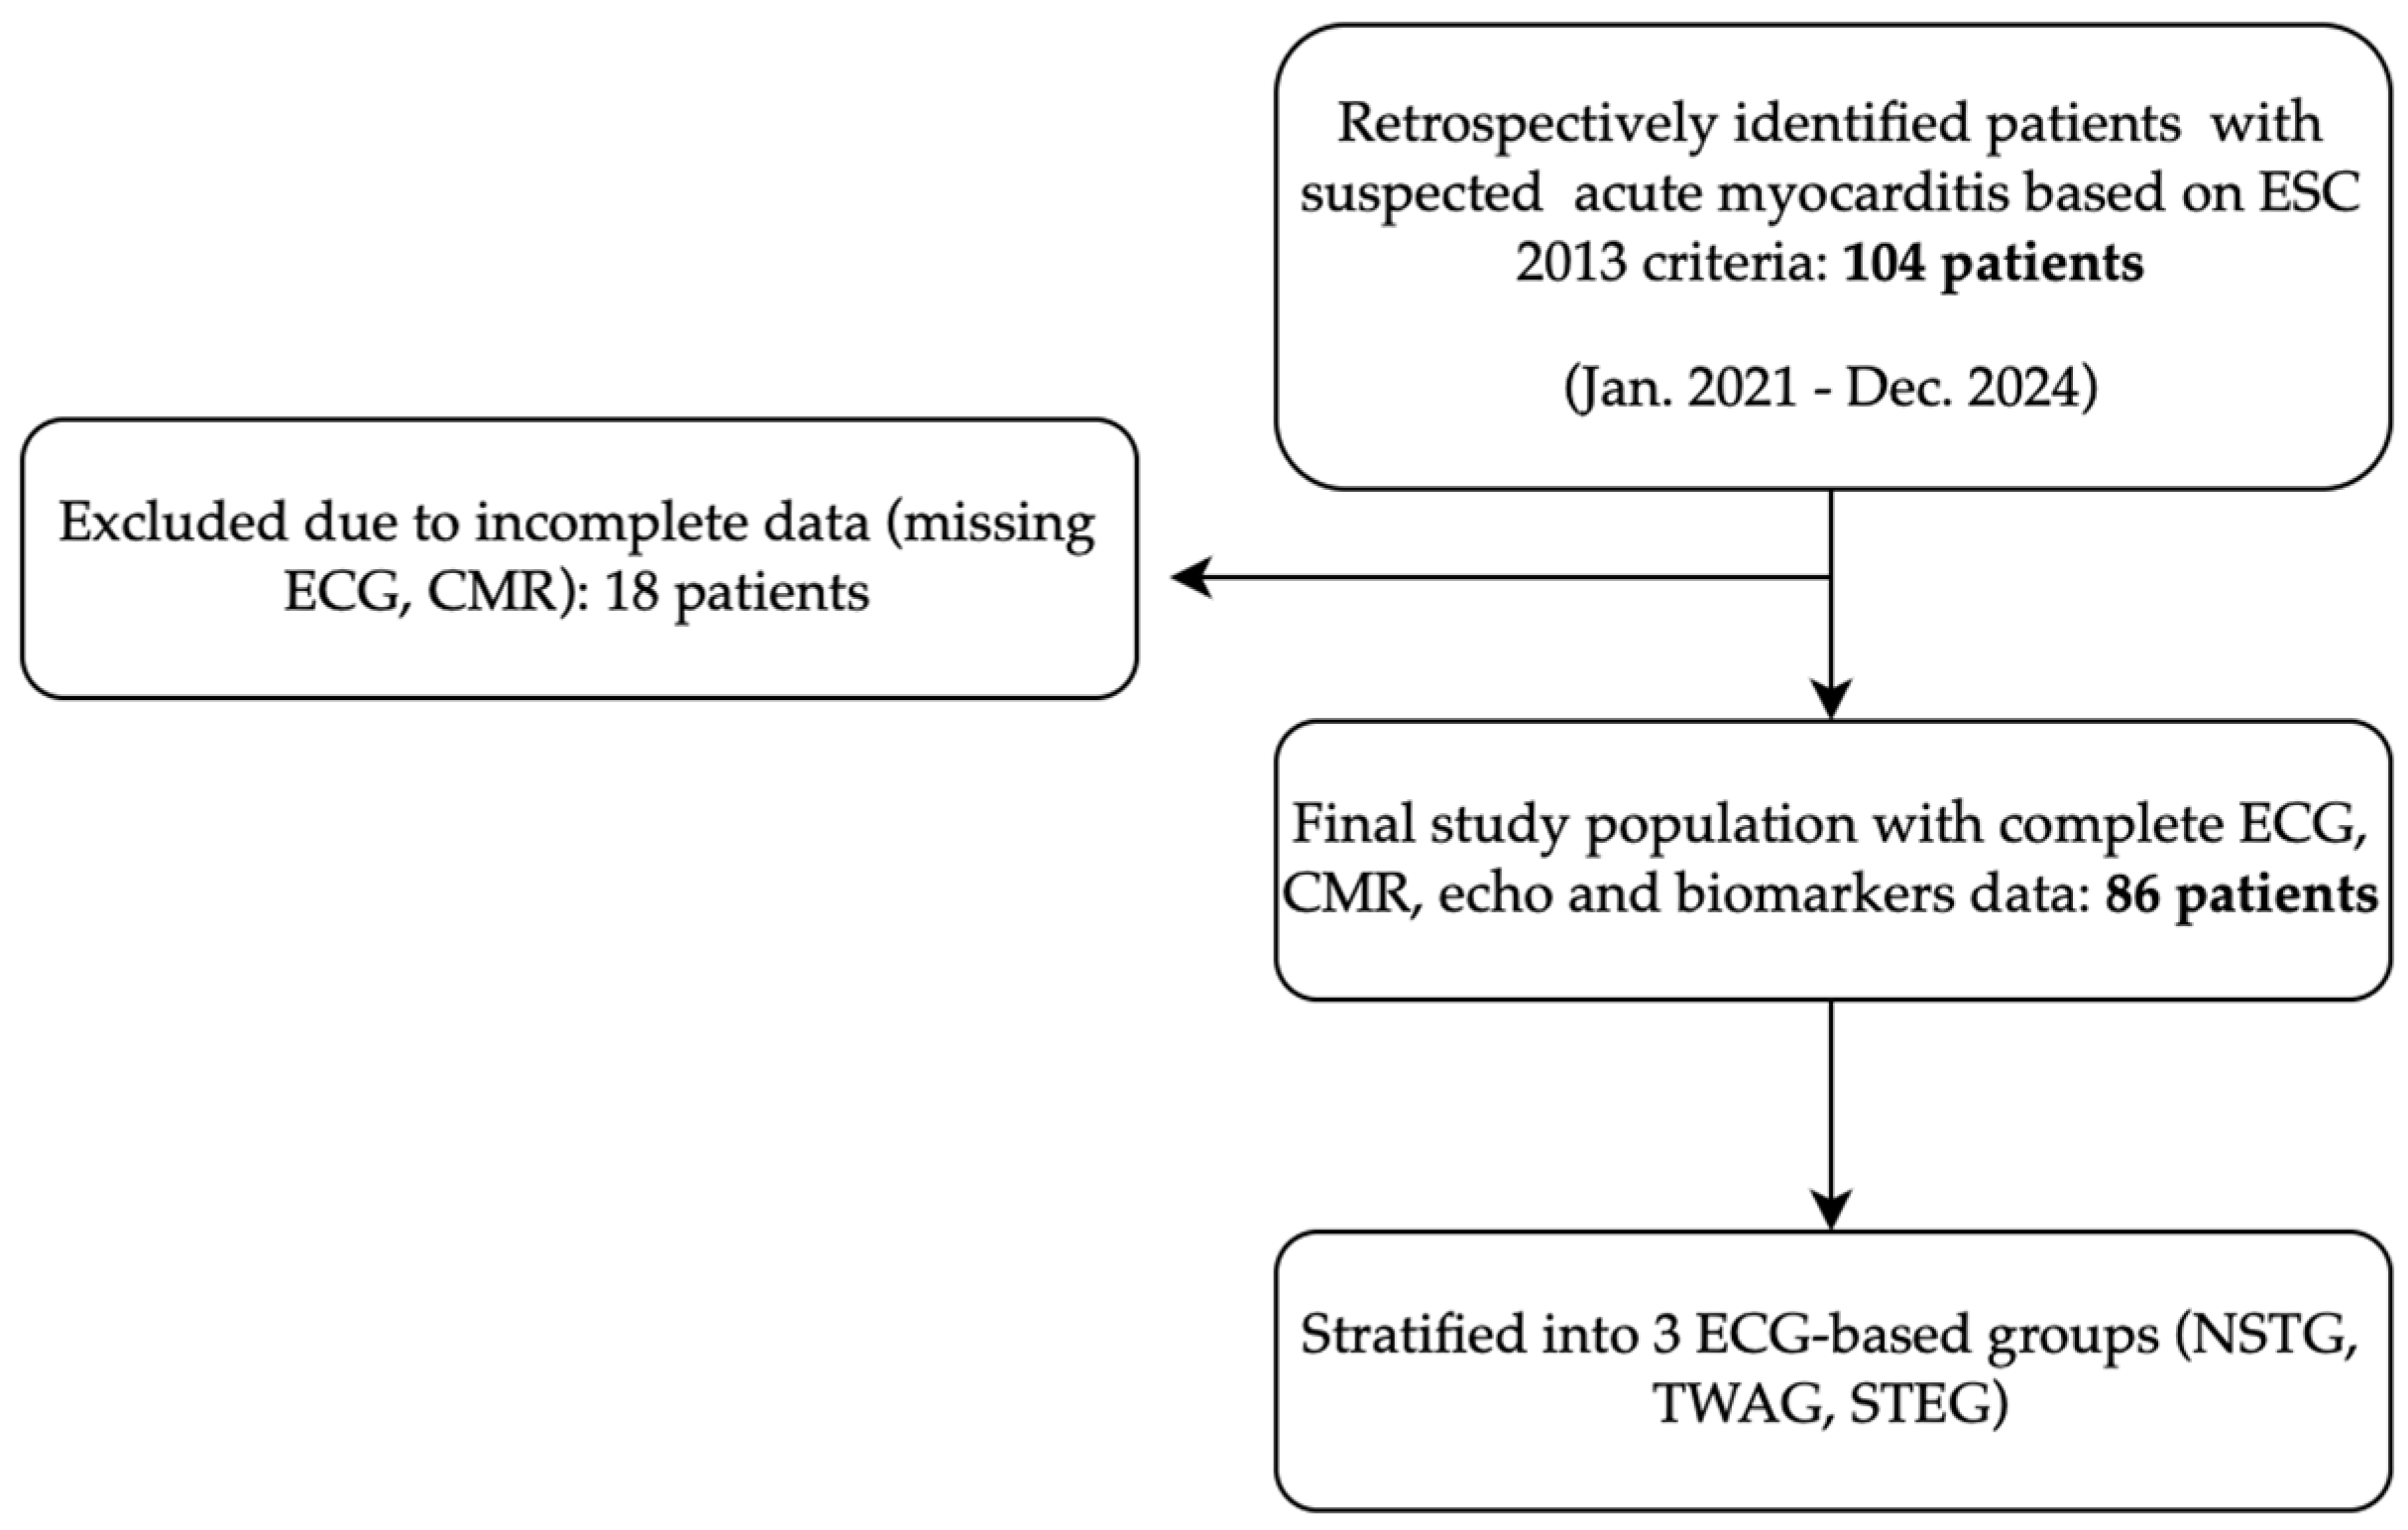

2. Materials and Methods

2.1. Study Design

2.2. Participants

3. Results

3.3.1. Electrocardiogram